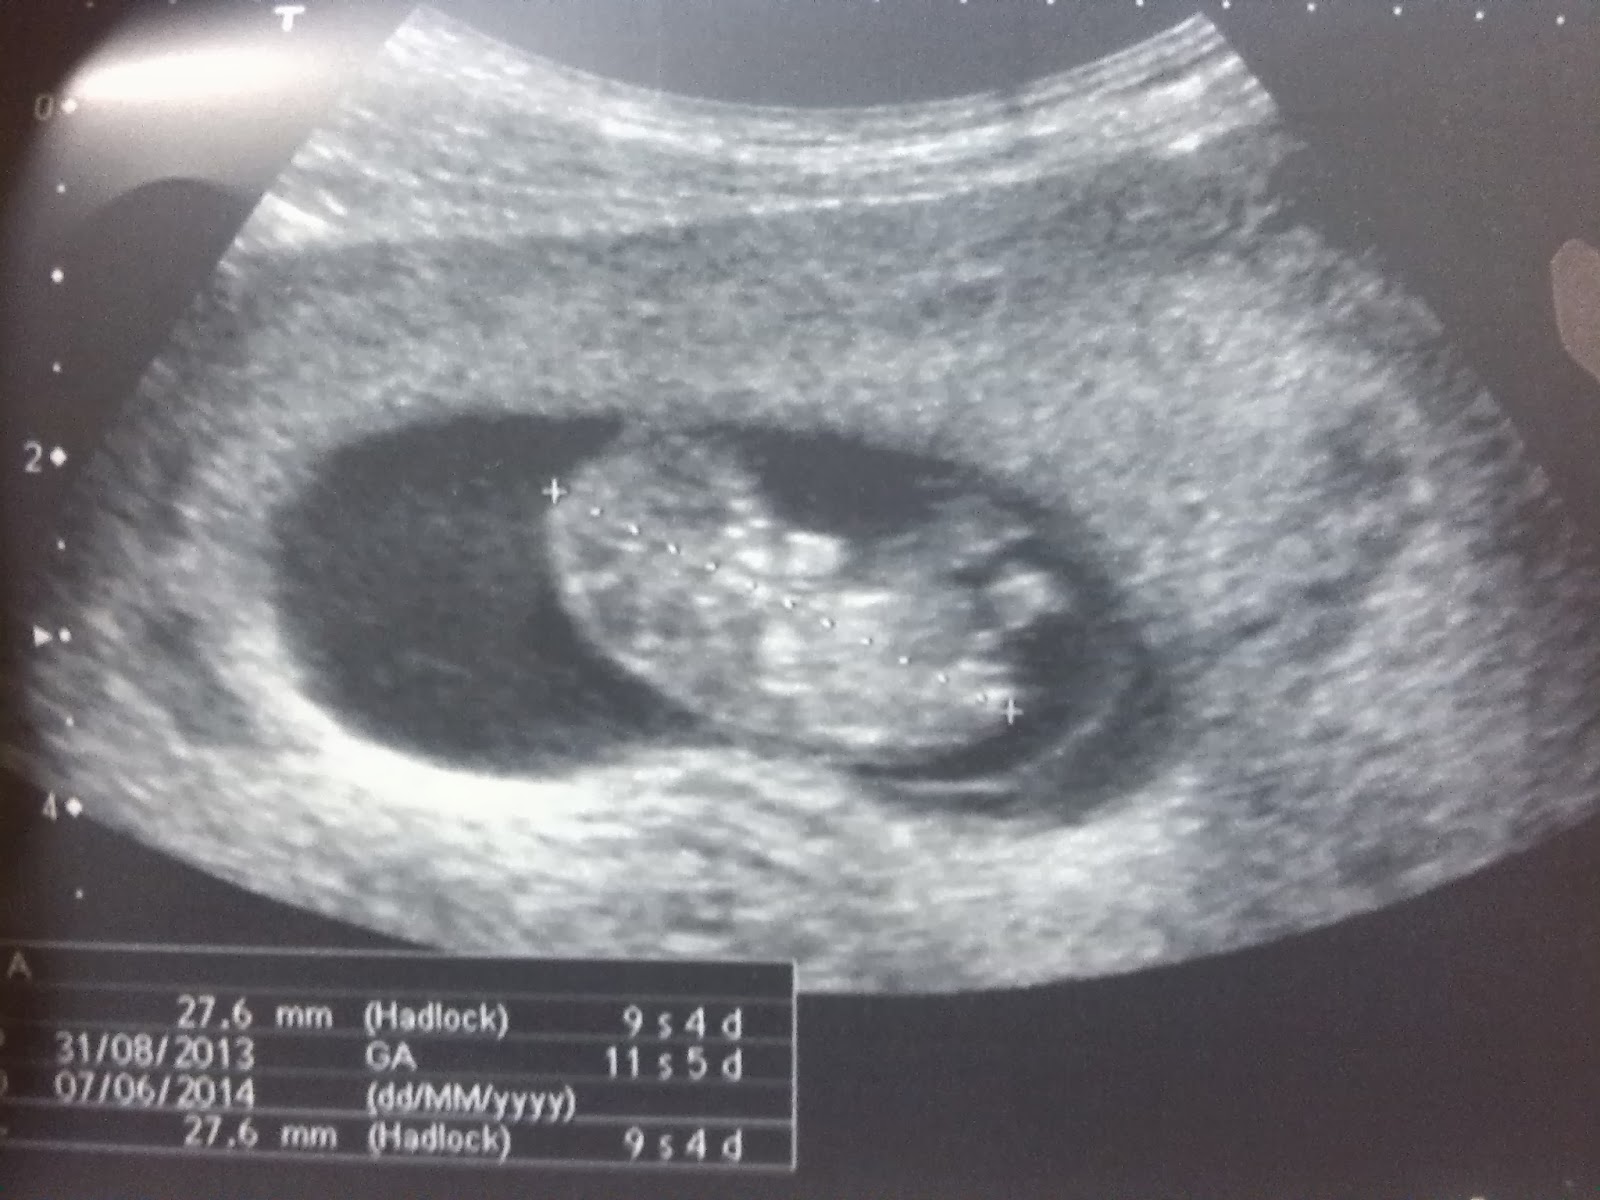

9+4

La ecografía correspondía a la semana 12 de embarazo, pero como tenía controlado cuando ovulé, intuía que estaba de 2 semanas menos y resultó que así fué. Me recalcularon la supuesta fecha de la regla como si me hubiera venido más tarde. El embrión medía 27 mm. y ese tamaño correspondía a 9+4 (9 semanas más 4 días). Para mi lo más emocionante, a parte de poder oir el corazón fué ver la ecografía, ver que si que está ahí.

Me gusta ver la ecografía, tocarme la barriguita y pensar... ¡¡estás ahiiiiiiiiiii, agárrate fuerte que en junio te quiero ver!! e inconscientemente me sale una sonrisita de alegría :)